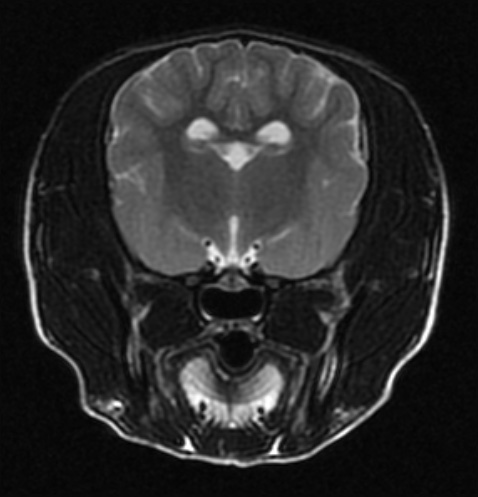

MRI는 자기장 내에서 신체에 고주파를 전사해 반향되는 전자기파를 측정 및 재구성하여 영상을 얻어 질병을 진단하는 검사로, 일반 방사선 검사(x-ray), 전단화 단층 촬영(CT)과 비교하여 방사선 피폭이 없고, 영상 대조도 및 해상도가 연부 조직과 뇌 검사에 뛰어난 장점을 가집니다. MRI는 뇌수두증이나 뇌종양 등 두개내 질환, 디스크탈출, 척수 질환 및 관절염과 인대 파열 등의 관절 질환의 평가에 유용하며 병변의 정확한 진단에 도움을 주고, 이를 통해 이후 빠른 내∙외과적인 치료를 가능하게 합니다.